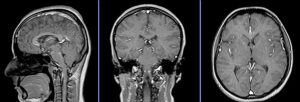

در دنیای پیچیده و پرشتاب پزشکی امروز، تشخیص دقیق و به موقع، کلید اصلی موفقیت درمان است. اما برای دیدن آنچه در اعماق بدن انسان پنهان شده و از چشم پزشک معالج دور مانده، به یک متخصص با ابزارهای شگفتانگیز نیاز داریم. اینجاست که رادیولوژیست، یا همان پزشک متخصص تصویربرداری، وارد صحنه میشود. او نه تنها یک عکسبردار، بلکه یک مفسر ماهر است؛ فردی که زبان خاموش تصاویر پزشکی را میداند و میتواند اسرار نهفته در تاریکی سونوگرافی، اشعه ایکس، سیتی اسکن و MRI را فاش کند.

تفسیر تصاویر پزشکی (قلب تخصص): مهمترین و حیاتیترین نقش او، تفسیر علمی و دقیق تصاویری است که توسط تکنسینهای رادیولوژی تهیه شدهاند. رادیولوژیست با دانش عمیق خود از آناتومی، فیزیولوژی و آسیبشناسی انسان، کوچکترین ناهنجاریها، تغییرات ساختاری و علائم بیماریها را در این تصاویر تشخیص میدهد.

رادیولوژیستها طیف وسیعی از بیماریها را تشخیص میدهند، از جمله: انواع شکستگیها و آسیبهای اسکلتی-عضلانی، تومورهای سرطانی و خوشخیم، بیماریهای قلبی و عروقی (مانند تنگی عروق)، مشکلات گوارشی، بیماریهای ریوی، اختلالات مغز و اعصاب و بیماریهای داخلی زنان و زایمان (به خصوص از طریق سونوگرافی).